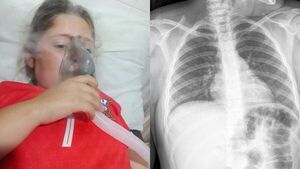

Piden ayuda para niña con epilepsia y problemas pulmonares

La familia Valenzuela, de General Delgado, busca reunir fondos para costear el tratamiento de su hija, cuyo cuadro de salud se agravó en las últimas semanas. [Leer más]